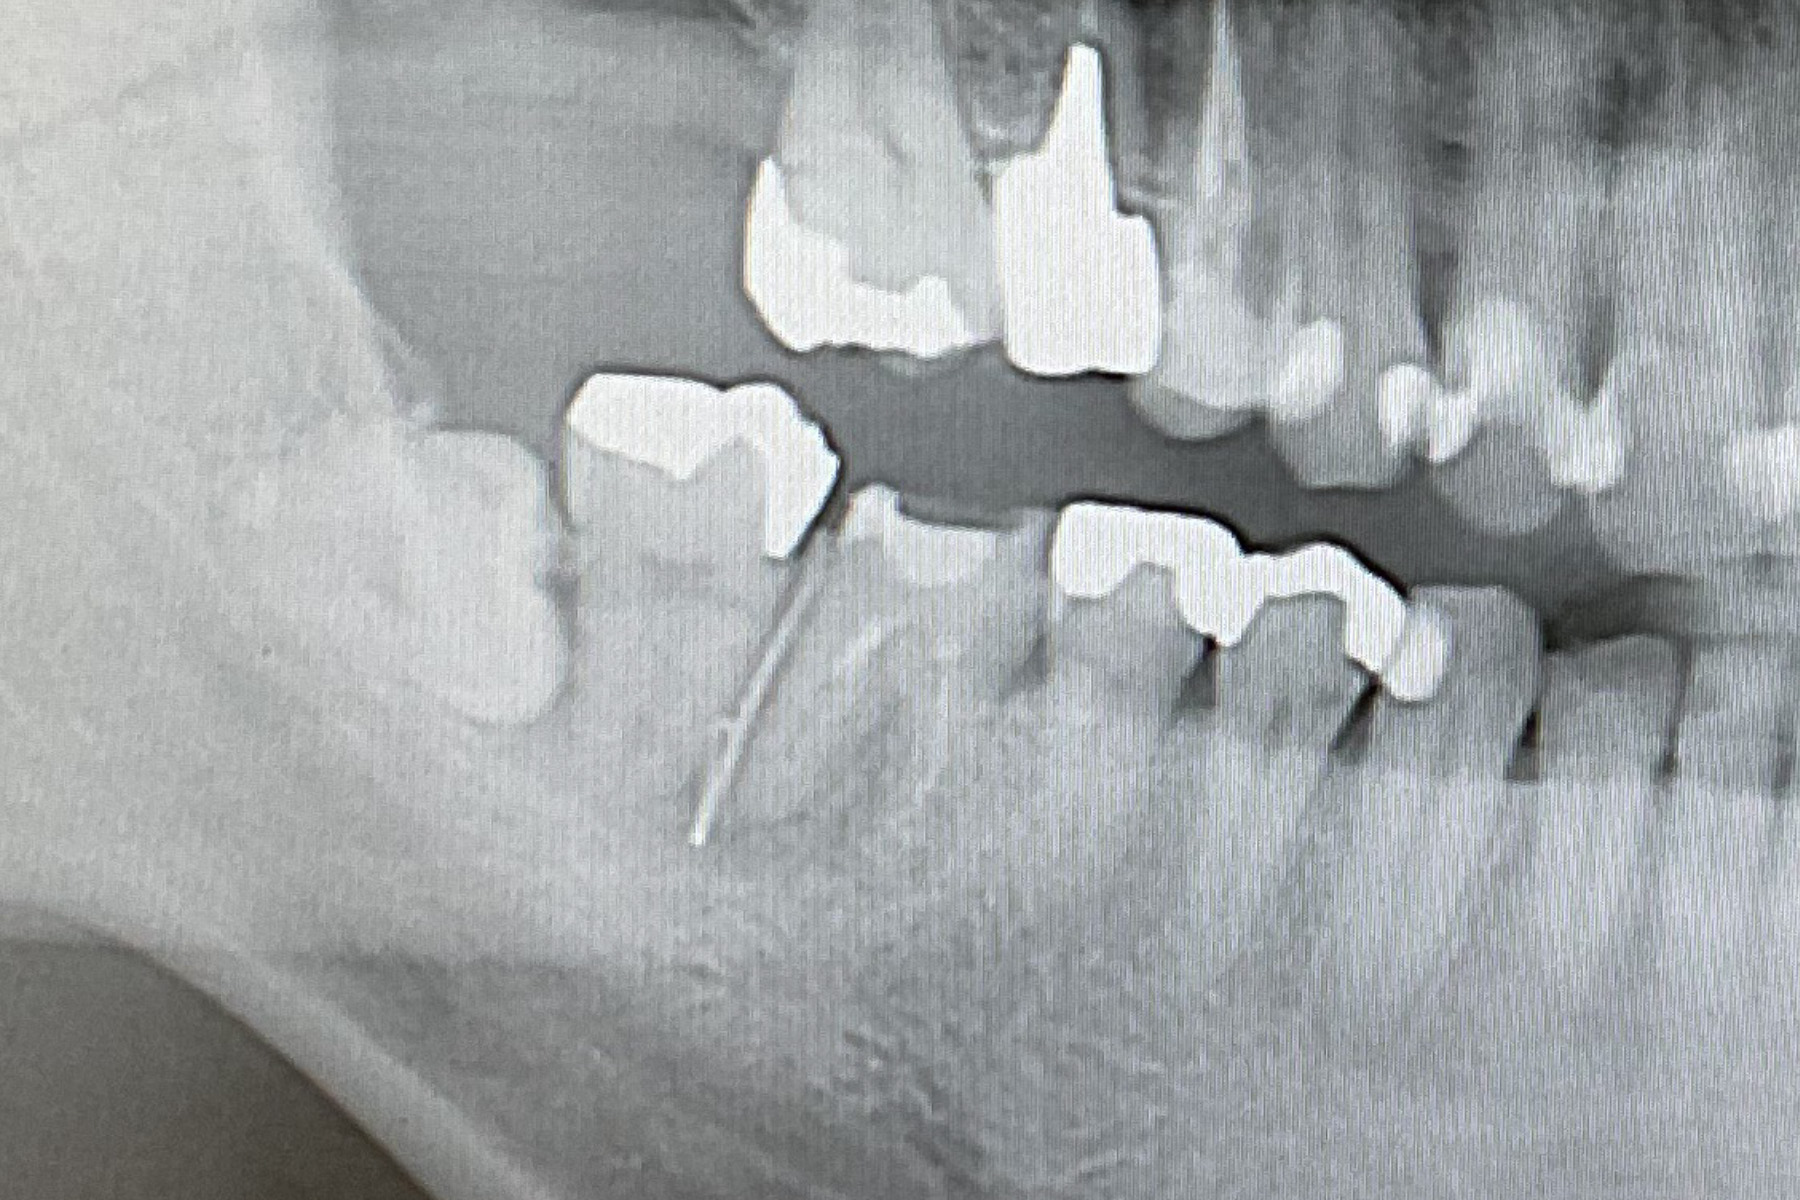

CASE16:抜歯即時インプラント

症例

CASE16